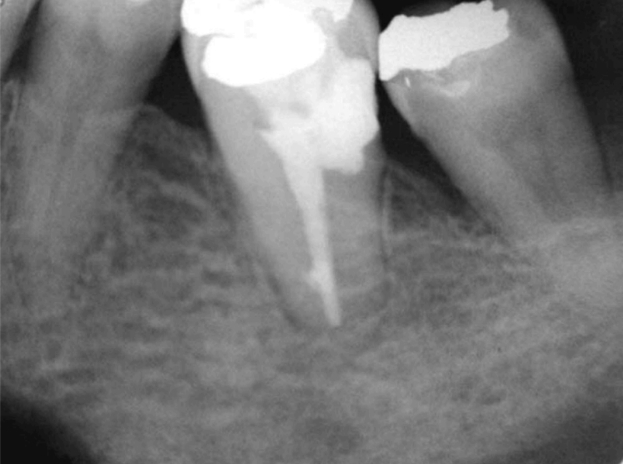

Контрольный осмотр через месяц показал, что пациент не испытывал никаких симптомов — отек и болезненность при перкуссии полностью исчезли. Через 6 месяцев зуб по-прежнему оставался асимптоматичным, пародонтальные карманы не наблюдались, подвижность зуба была в пределах нормы. Через 15 месяцев на рентгенограммах было видно адекватное закрытие супракрестальной перфорации и восстановление периапикальной области (рис. 2 и 3); зуб оставался без симптомов, а мягкие ткани имели нормальный вид. И врач, и пациент сочли результат удовлетворительным.

Рисунок 2. Периапикальная рентгенограмма — наблюдение через 15 месяцев.

Рисунок 3. Периапикальная рентгенограмма (негативное изображение) — наблюдение через 15 месяцев.

Данный случай можно считать успешным как в клиническом, так и в рентгенологическом аспекте, поскольку уже через 6 месяцев после лечения на месте перфорации было видно заживление, а пациент не предъявлял жалоб на наличие свищей, отёков или болей. Через 15 месяцев зуб по-прежнему оставался асимптоматичным, рентгенологически зуб был в норме, и пациент был доволен возможностью сохранить зуб.